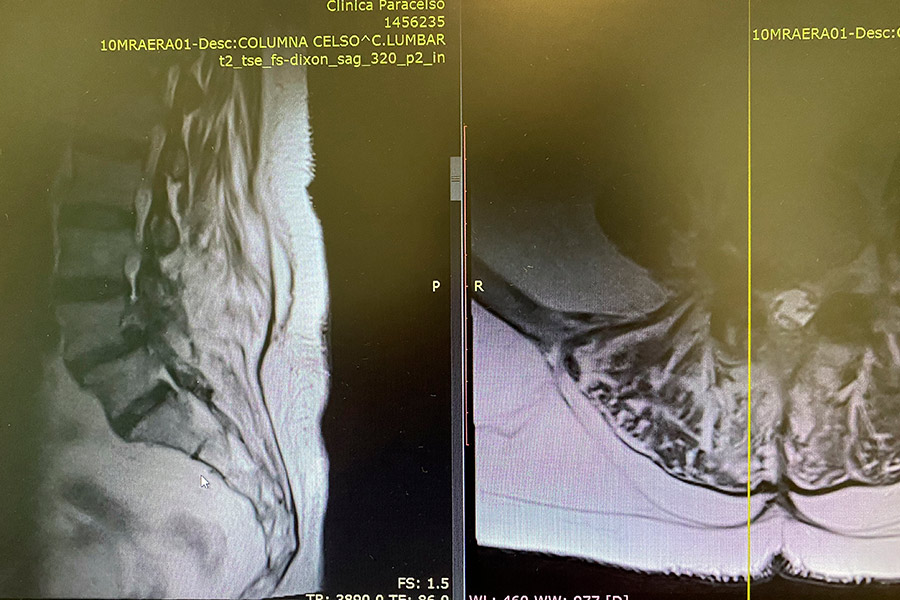

Paciente de 68 años, operada hace 8/9 años entre la 4º y 5º vértrebra lumbar.

Tras estudiar y revisar el caso en profundidad, se descubre una recidiva de la hernia que sale por donde sale el nervio.

Hernia-discal-foramidal-josefa-carro-preop